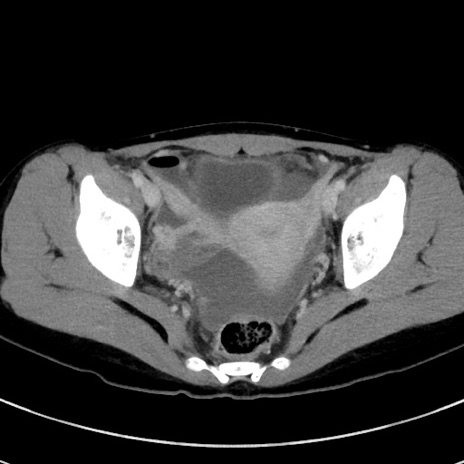

症例17(横断像)

【症例】20歳代女性

【主訴】嘔吐、下腹部痛

【現病歴】昨日夕食後に嘔吐し下腹部痛が出現。本日になっても嘔吐持続し改善しないため来院。

【身体所見】意識清明、BT 37.2℃、BP 108/67mmHg、腹部:平坦、やや硬、下腹部正中から右にかけて圧痛あり、反跳痛軽度あり、tapping pain(+)。

【データ】WBC 13600、CRP 14.94